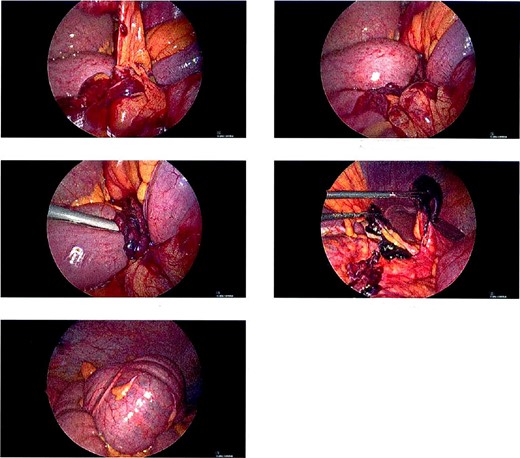

A 68-year-old male with a history of hypertension and no past surgical intervention presented with 2 days of diffuse abdominal pain, anorexia, and nausea. On admission, his vitals included a temperature of 98.2°F, BP of 149/79, pulse of 64, and SpO2 of 97% with a mildly distended abdomen with tenderness in the umbilical and epigastric regions. The labs were unremarkable. CTA/P showed two separate areas of mesenteric swirling: one contiguous to the distal small bowel, resulting in small bowel obstruction, and another at the distal transverse colon (Fig. 1A–C). The cecum was noted to be in the right upper quadrant. The patient was emergently taken to the OR and underwent a diagnostic laparoscopy. A cecal bascule was noted in addition to an internal hernia caused by a thick adhesive necrotic band arising from the colonic mesentery and omentum (Fig. 2). The bowel was viable, and the band was resected. The transverse colon was tortuous, but no hernia was seen. The cecum was brought down to the right lower quadrant, and a cecopexy to the abdominal wall was performed. The patient had an unremarkable postoperative course and was discharged on postoperativhernia was seen. The cecum was brought down to the right lower quadrant, and a cecopexy to the abdominal wall was performed. The patient had an unremarkable postoperative course and was discharged on postoperative Day 2.

(A and B) Two separate CT images showing mesenteric swirling in distal small bowel and colon. (C) CT image showing severe luminal narrowing of distal transverse colon.

Intraoperative pictures of thick necrotic/adhesive band arising from colon mesentery entrapping band. Cecal bascule found in the RUQ.